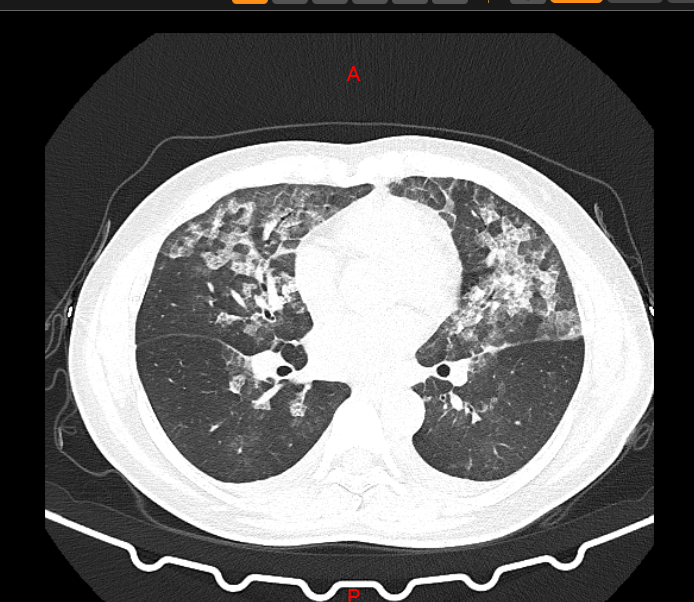

↑↑张女士肺部CT

肺部CT均呈毛玻璃影,难道是新冠病毒?

郑州市中心医院高新区医院管床医师李凤芝反复追问病史,两位均无流行病学史,隔离病区主任张小红看完患者的影像学资料及各项检查结果后说:“这两位患者考虑为过敏性肺泡炎,现在我们必须详细询问病史,了解过敏的物质。”

张小红主任:“张女士和王女士是84消毒液引起的过敏性肺泡炎!”经过3天的抗过敏治疗后复查胸部CT,影像基本恢复正常!